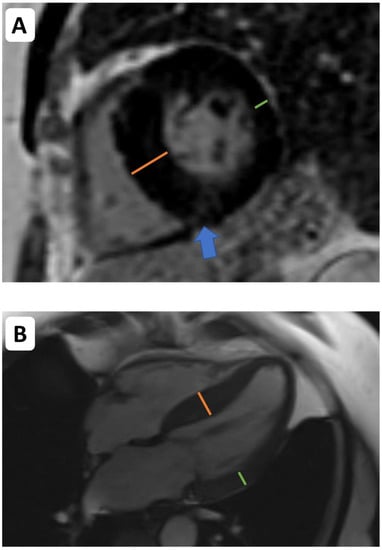

- Cartlidge, T.R.; Bing, R.; Kwiecinski, J.; Guzzetti, E.; Pawade, T.A.; Doris, M.K.; Adamson, P.D.; Massera, D.; Lembo, M.; Peeters, F.; et al. Contrast-enhanced computed tomography assessment of aortic stenosis. Heart 2021, 107, 1905–1911. [Google Scholar] [CrossRef]